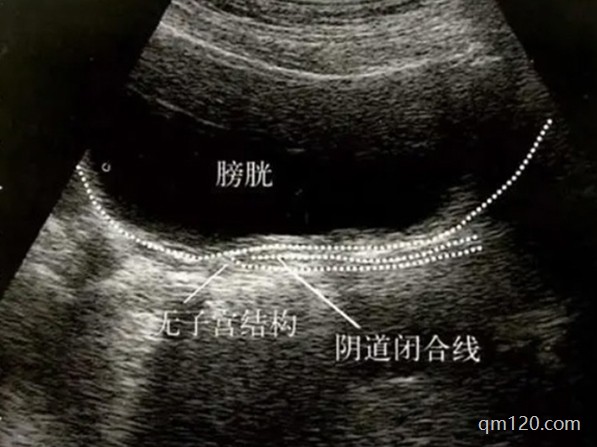

先天性無子宮的女性無法通過常規(guī)試管嬰兒技術(shù)生育。試管嬰兒技術(shù)需要子宮作為胚胎著床和發(fā)育的場所。但是,通過第三方輔助生殖,例如試管嬰兒結(jié)合第三方妊娠(俗稱“助孕”...